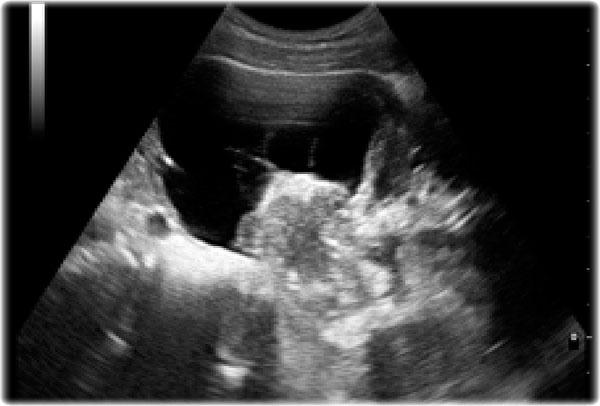

Đây là hình ảnh của một bé gái 1,5 tuổi có khối u sờ thấy được ở bụng trái.

Siêu âm cho thấy một khối u lớn cấu thành bởi vô số nang, xuất phát từ thận trái.

Trên ảnh MRI mặt phẳng trán chuỗi xung T2W, các nang được hiển thị rõ ràng.

Phần còn lại của thận trái nằm ở phía đuôi của khối u.

Kết quả giải phẫu bệnh xác định là u nguyên bào thận dạng nang biệt hóa một phần.